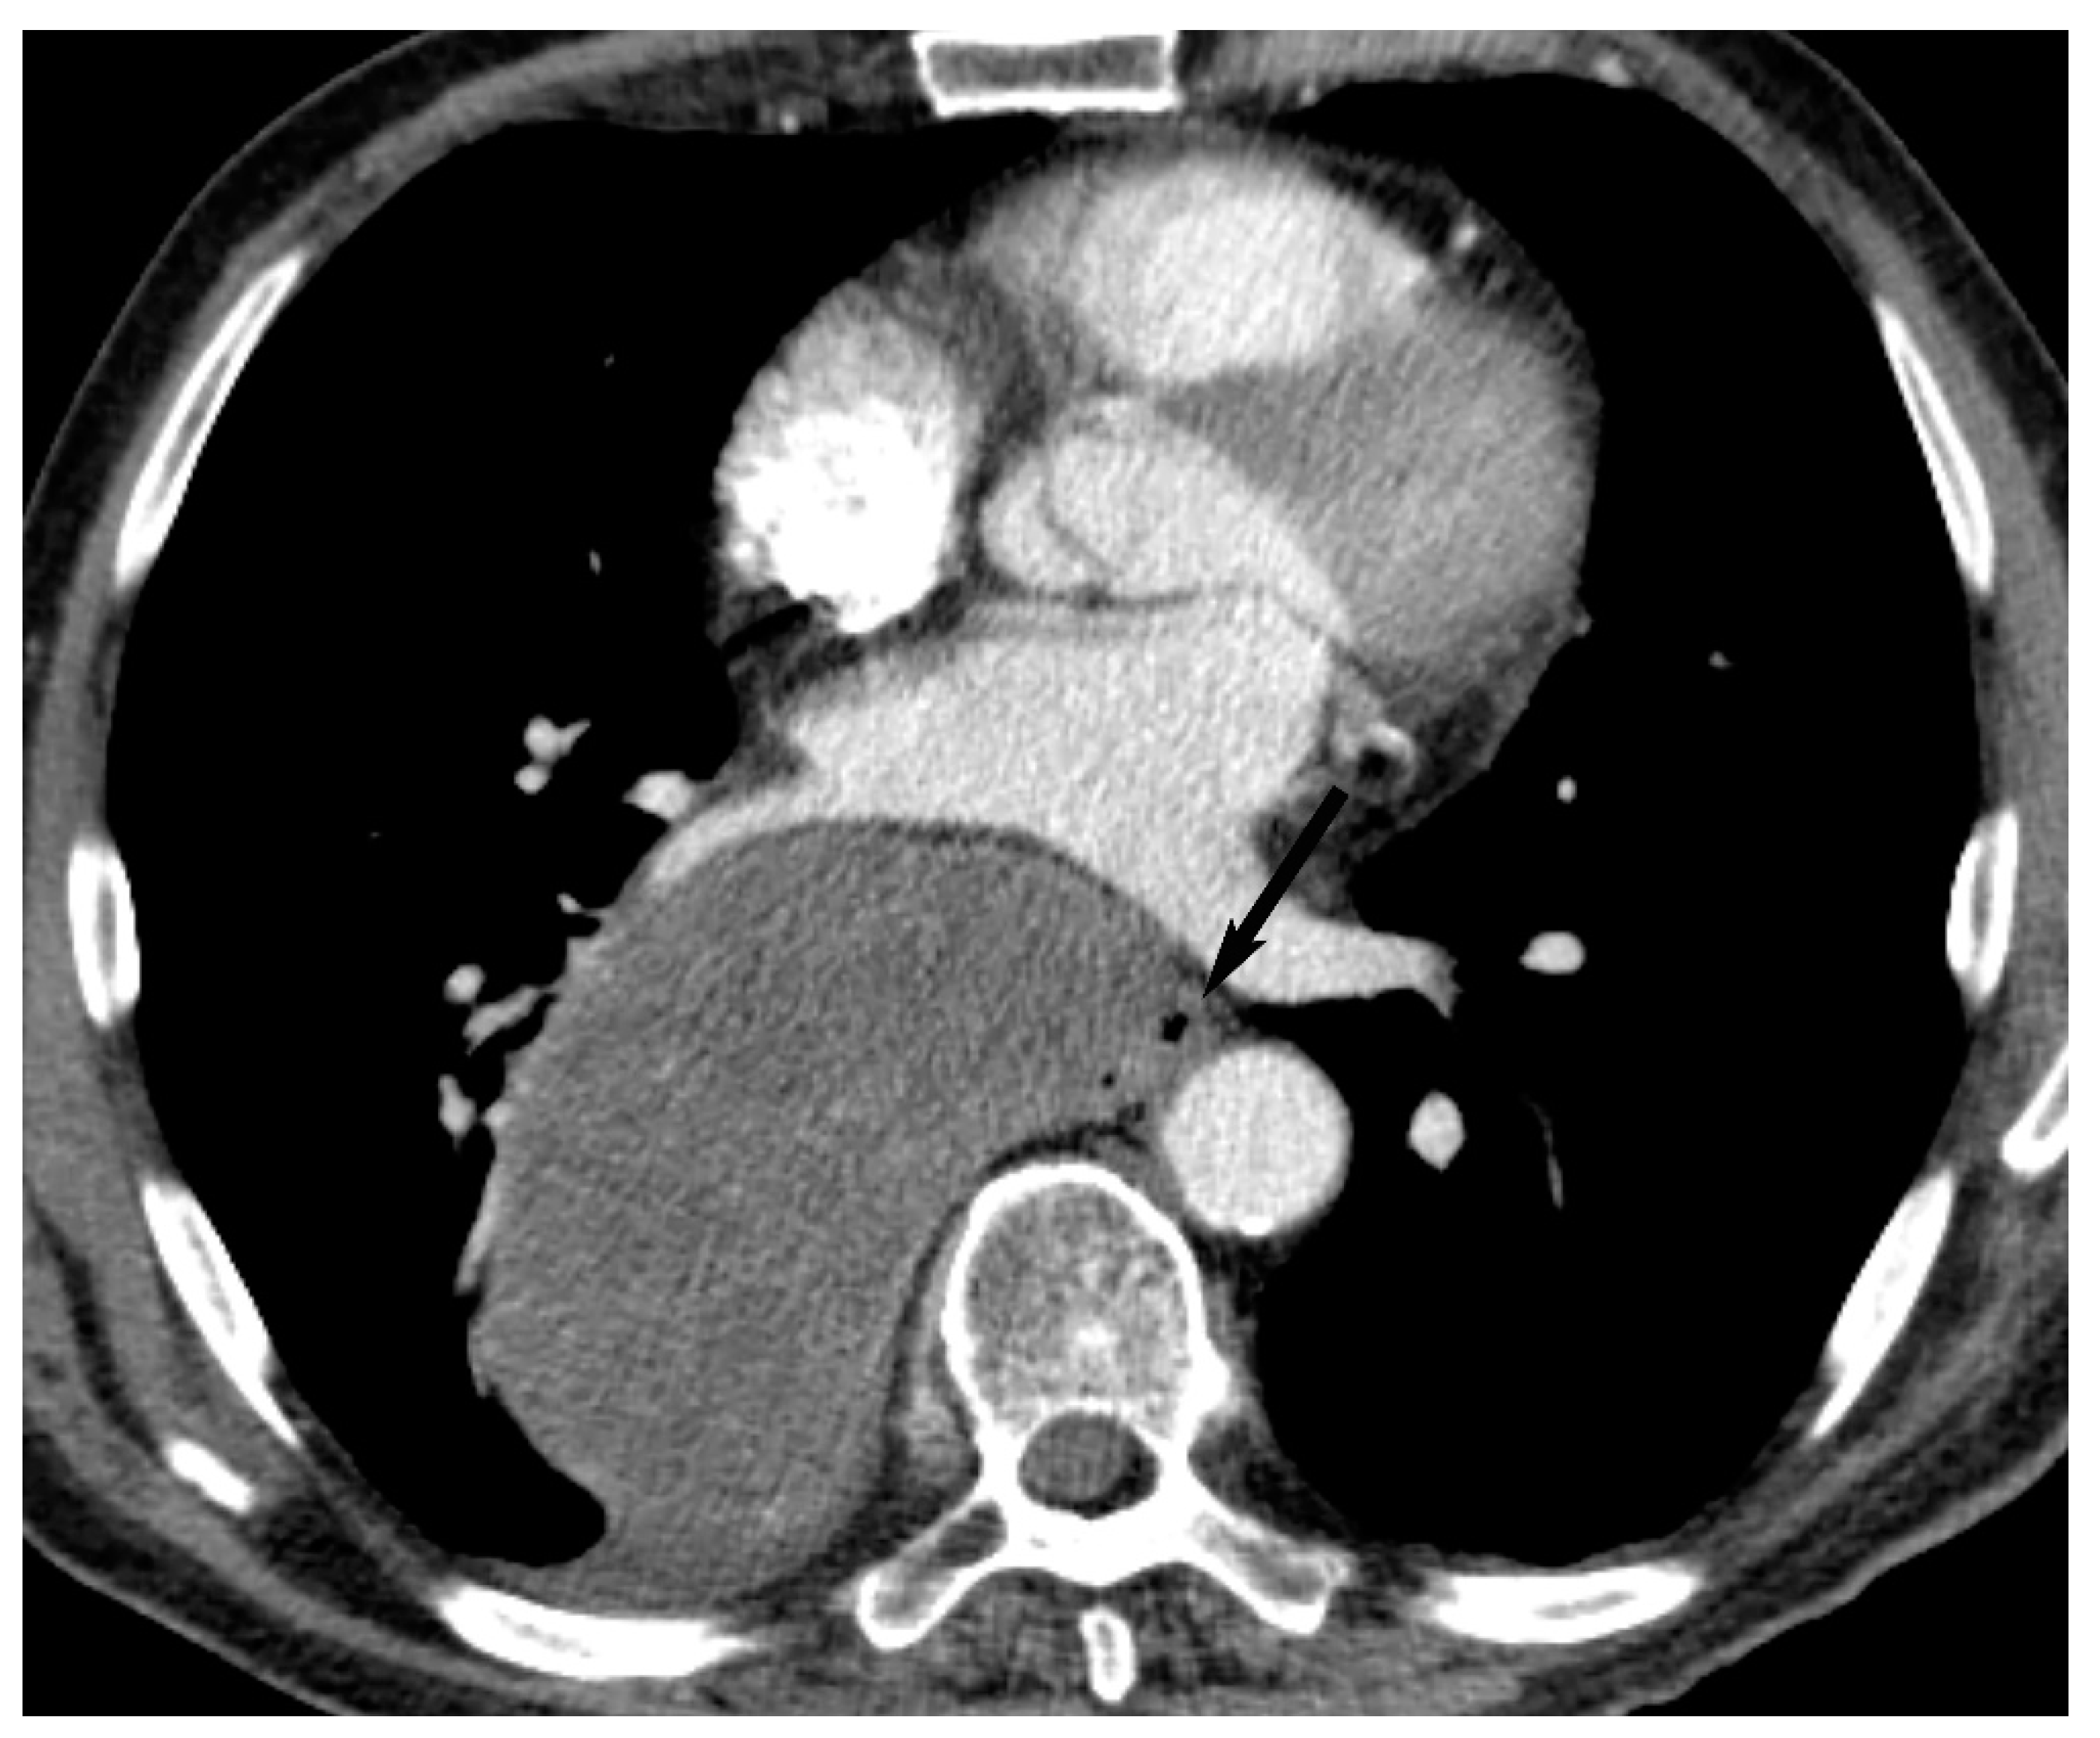

6. Lymphoma

8. Cystic Lesions